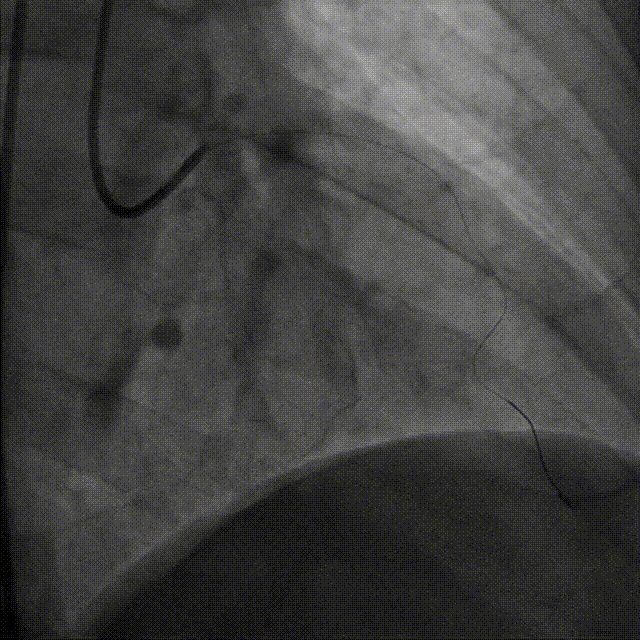

谷兴华教授 山东大学齐鲁医院 锚定终身获益,重视首次干预选择:心脏瓣膜病介入中心成立2年多来,中心核心目标始终保证在解决即刻病症的基础上,护航患者的全生命周期健康管理。 摆在眼前的实际是日益年轻化的患者群体,这意味着我们从手术伊始,就必须将患者未来数十年的生活质量和再次干预风险纳入核心考量,主动规划长远的健康路径。此次患者选择更具耐久的新型干瓣技术,力求减少患者未来再次干预的风险。同时,通过“TAVR+PCI一站式手术”这样的团队协作模式,系统性地处理多重心血管问题,避免分次手术的负担与风险,这正是我们中心一直秉持的“心脏瓣膜病全生命周期管理”理念的实践。让我们一起探索从“治已病”真正迈向“管长远”,让更多的患者获益! 病例特点速览 本次救治的患者,病情呈现“基础病交织、多病变叠加、锚定风险高”三大核心特征。患者为65岁,女性,病变特点TypeI型二叶瓣、轻度钙化,锚定风险大;同时患有冠状动脉粥样硬化性心脏病、慢阻肺(COPD);既往有长期吸烟饮酒史、脑梗死病史、高血压病史、乙肝小三阳病史及腹股沟疝修补手术史,患者STS评分9.32%,外科手术高危,经齐鲁医院瓣膜中心团队评估认为:局麻下“一站式TAVR+PCI”为最优治疗方案,结合患者较年轻,可选择具有长期耐久性的干瓣。 患者病史 主诉:活动后胸闷、憋喘余,加重20余天 既往史:30年前确诊乙肝小三阳,否认其他传染病史;有右腹股沟疝修补手术史,高血压病史,近期规律服药控制。 现病史:患者1年前出现活动后胸闷、憋喘,休息可缓解,为进一步诊治。2月前因“突发意识模糊、口齿不清”于当地医院入院,诊断为“急性脑梗死”,予以微创介入取栓治疗,恢复可,未遗留后遗症。20天前于当地医院再次入院行脑血管支架植入术,术后出现胸闷、憋喘,伴大汗,行心脏超声提示主动脉瓣重度狭窄,并行冠脉造影检查,予以药物治疗。10天前就诊于我院复查心脏超声提示二叶式主动脉瓣,主动脉瓣狭窄(重度)并反流(轻度)。患者现仍感胸闷,双上臂疼痛不适,咳嗽咳痰,日常活动受限。为行进一步治疗就诊于我院,门诊以“主动脉瓣狭窄、冠状动脉粥样硬化性心脏病”收入院; 个人史:吸烟50年,饮酒50年; 体格检查:体温:36℃,脉搏:67次/分,呼吸:18次/分,血压:143/76mmHg; 术前超声提示: 二叶式主动脉瓣主动脉瓣狭窄(重度)并反流(轻度);升主动脉扩张、左心扩大三尖瓣反流(少量);左室充盈异常;CW测最大压差86mmHg,平均压差43mmHg,最大血流速度463cm/s,连续方程法估测主动脉瓣口面积0.78cm² 术前CT评估 Type1型二叶瓣,轻度钙化、左右融合,主动脉瓣环径25.3mm,LVOT直径25.5mm,鱼嘴空间约26.6mm,主要靠瓣环锚定。窦部空间大、左右融合,VTC空间足够,无冠脉风险 ;左室内径正常,主动脉瓣环水平夹角49.6°。外周双侧入路内径可,髂外动脉存在散在钙化、双侧入路能够支持20F大鞘通过,右股低分叉,主动脉弓距弓角可。 个性化手术策略:局麻一站式方案+创新瓣膜精准适配 入路选择:主入路:右侧股动脉(右股分叉上方1cm处穿刺);辅入路:左侧股动脉;器械:20F大鞘; 手术流程规划:局麻下行同期一站式TAVR+PCI,植入ProStyle A®预装干瓣; 瓣膜选型与预处理:瓣膜型号:ProStyle A® AV32;不预扩; 定位与释放方案:初始定位:瓣上3mm处释放,瓣膜自然下滑至工作位,最终目标“0-瓣下5mm位”。 手术过程:局麻一站式操作+创新瓣膜植入,无缝衔接 手术团队按预设方案稳步推进,实现TAVR、PCI与ProStyle A®干瓣植入的无缝衔接: 1.术前准备:完成影像评估、血管通路建立,确认ProStyle A® AV32瓣膜状态; 2.PCI治疗:通过主入路完成左冠造影,前降支、对角支明显狭窄,精准植入两枚支架,恢复冠脉血供; 左冠造影,前降支、对角支病变 PCI后造影,病变血管充盈良好 3.主动脉根部造影:确认主动脉根部解剖结构,并精准跨瓣; 主动脉根部造影 精准跨瓣 4.干瓣植入:将瓣膜输送过弓、过瓣,并精准定位; 输送系统柔顺过弓 精准定位 5.术中评估:释放瓣膜至工作状态,再次造影评估,位置满意,完全释放瓣膜; 工作位评估 32号瓣膜稳定脱钩 6.释放后造影:可见瓣膜位置满意、形态良好,无明显瓣周漏。 最终造影,位置形态良好,无瓣周漏 术后超声探查:位置(瓣下4mm)、形态良好,无瓣周漏,PGmean=10mmHg。 此次手术的成功,体现了山东大学齐鲁医院心脏瓣膜病介入中心秉承的“心脏瓣膜病全生命周期管理”的理念和团队协作的临床能力。面对低龄高风险复杂病例,团队通过术前充分评估、术中精细操作,结合具有长期耐久性的干瓣技术,以一站式方案改善患者症状、提高生活质量并延长寿命,为类似病例的诊疗提供宝贵经验。 专家简介 谷兴华 山东大学齐鲁医院(点击查看专家详细简历)